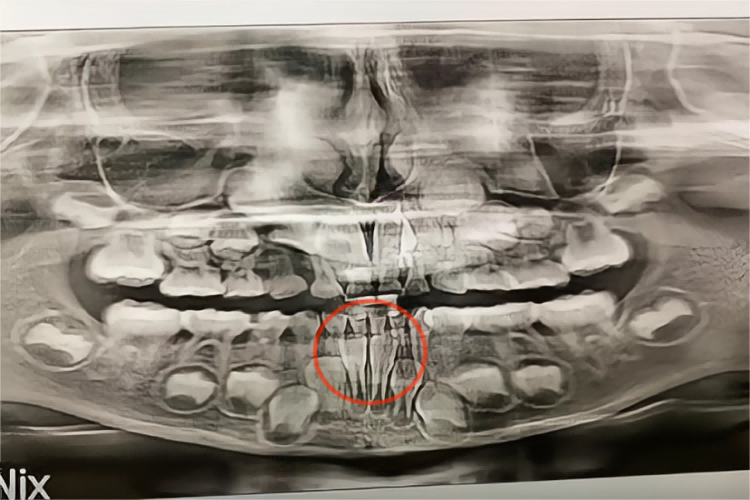

儿童牙齿牙片出现异常表现主要见于龋齿及乳牙滞留,儿童龋齿可见牙片上单个或多个牙齿釉面出现缺损,牙体硬组织显示出透射度增大的阴影,局部可有龋洞。儿童发生乳牙滞留时,可见双排牙现象,常见于下颌乳中切牙滞留,恒中切牙于乳中切牙舌侧萌出。